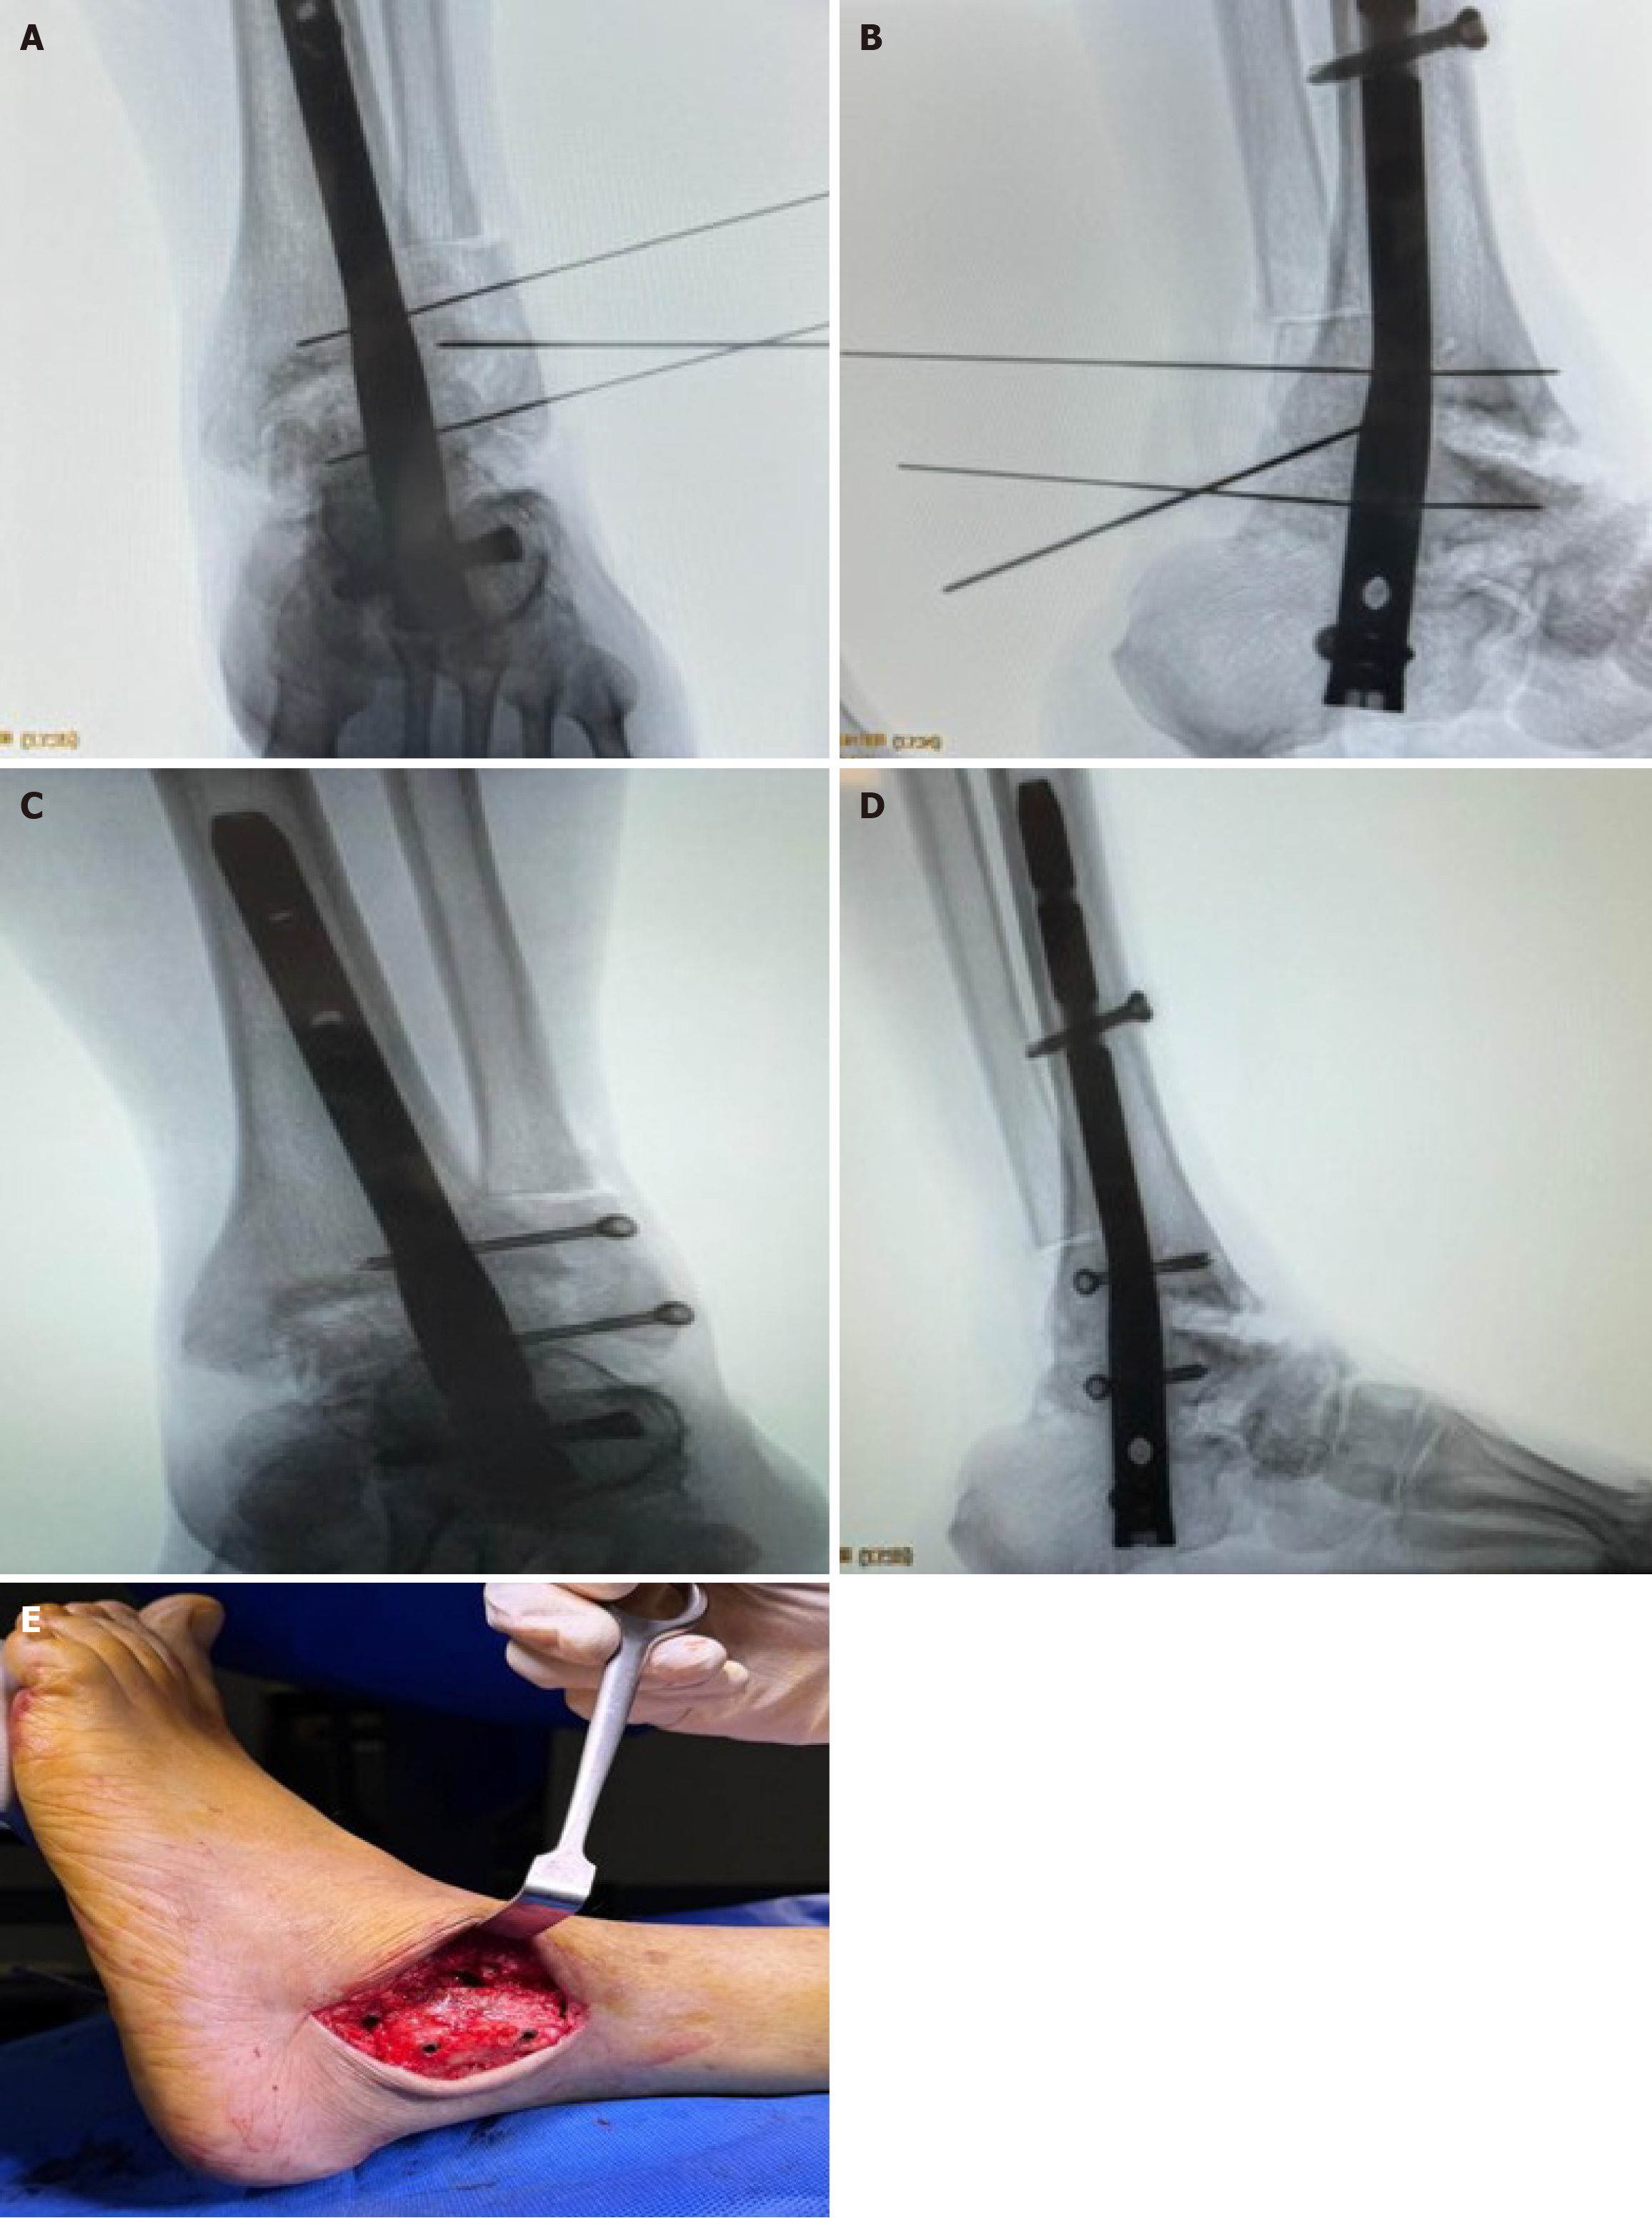

Step 1: Transmalleolar approach with periosteal preservation: The surgical approach was initiated through a lateral transmalleolar incision with a controlled lateral malleolar osteotomy performed approximately 2-4 cm proximal to the ankle joint line using an oscillating saw with the cut made perpendicular to the long axis of the fibula. The critical innovation involves opening the syndesmosis from anterior to facilitate preparation, followed by careful sliding and eversion of the fibula downward while maintaining its attachment to all related anatomical structures. Meticulous attention was paid to preserving the periosteal attachment and vascular supply to the entire distal osteotomized fragment, ensuring the fibular segment remained viable as a vascularized flap. This was achieved by careful subperiosteal dissection and protection of the perforating branches of the peroneal artery. This technique allows the preserved lateral malleolus to be retracted posteriorly using a Hohmann retractor, providing excellent visualization and access to both the ankle and subtalar joint complexes while maintaining the biological viability of the malleolar fragment for subsequent reconstruction and enhanced healing potential (Figures 1 and 2).

Step 3: Guide wire insertion and retrograde intramedullary nail placement: Under fluoroscopic guidance a guide wire was inserted through the plantar aspect of the calcaneus and advanced across the subtalar and ankle joints into the tibial medullary canal. Following sequential reaming, an appropriately sized retrograde intramedullary nail was inserted and advanced until adequate purchase was achieved in the tibial metaphysis with final positioning confirmed fluoroscopically (Figure 3).

Step 6: Fibular reduction and “trap door” fixation: The lateral malleolus was anatomically reduced and temporarily secured with cannulated guide wires under fluoroscopic guidance. Two cortical screws were then inserted in a posteroanterior direction at approximately 18-20 degrees, similar to syndesmotic screw placement but positioned to avoid interference with the intramedullary nail. This innovative “trap door” technique transforms the preserved fibular fragment into a multifunctional construct that provides: (1) Enhanced mechanical stability through tibiofibular compression; (2) Biological augmentation by creating a sealed chamber for the BMA and allograft; and (3) Additional fusion surface area between the fibula, tibia, and talus (Figure 6).